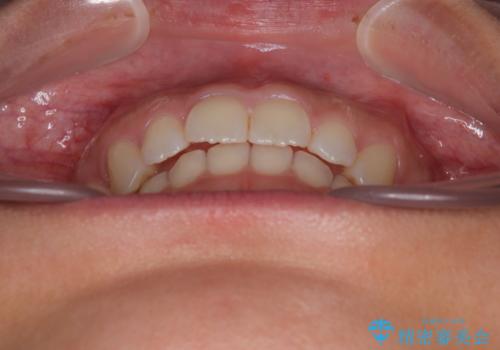

- 上の前歯が前方に飛び出していることを気にして来院された患者様です。

奥歯の咬み合わせをチェックすると、上顎歯列が相対的に前方に位置しているため、補助装置を用いて上顎歯列を確実に後方に移動させ、インビザラインで歯列を整えて行くこととしました。

インビザライン単体でも同様の結果が得られる可能性がありますが、万が一奥歯がうまく後方移動できなかった場合、リカバリーが非常に大変となるため、事前に補助装置を併用して確実に結果が得られるように工夫をしています。